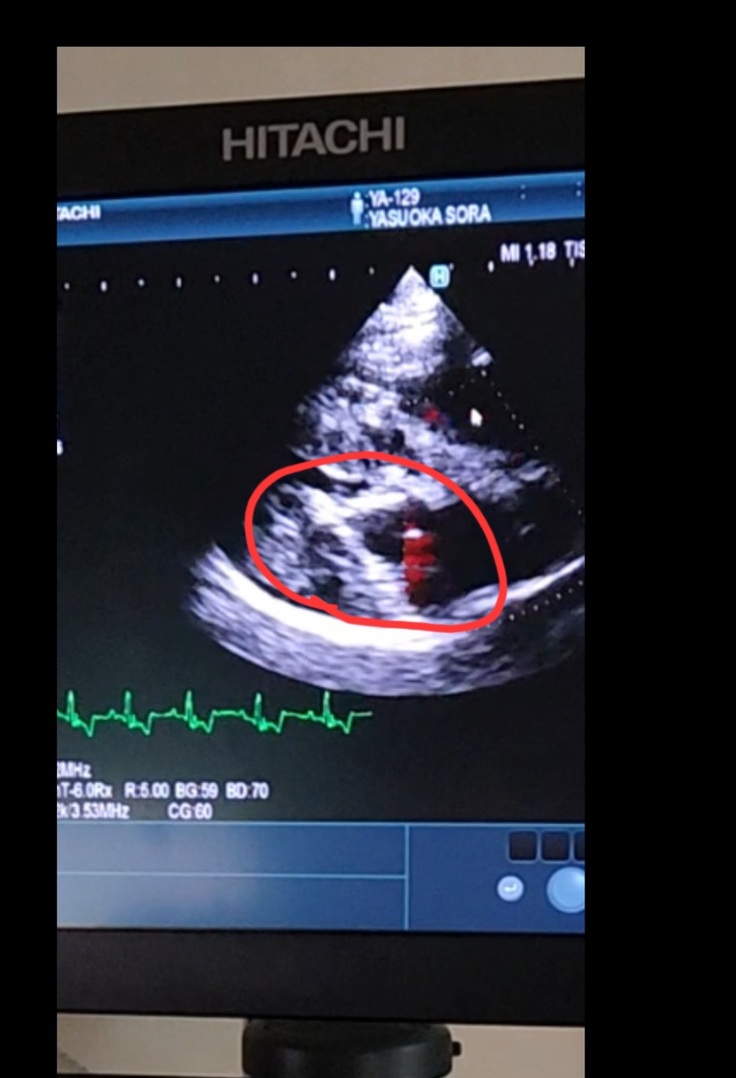

本日4月11日で空は僧帽弁閉鎖不全症の心臓手術より丸二年と成りました。

形成された心臓の弁は今もピッタリ閉じています。